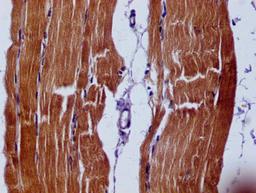

IHC image of CSB-MA021780A0m diluted at 1:60 and staining in paraffin-embedded human skeletal muscle tissue performed on a Leica BondTM system. After dewaxing and hydration, antigen retrieval was mediated by high pressure in a citrate buffer (pH 6.0). Section was blocked with 10% normal goat serum 30min at RT. Then primary antibody (1% BSA) was incubated at 4°C overnight. The primary is detected by a biotinylated secondary antibody and visualized using an HRP conjugated SP system.